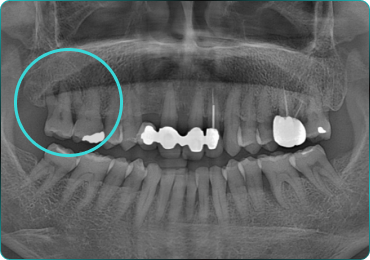

67세 여성

Before